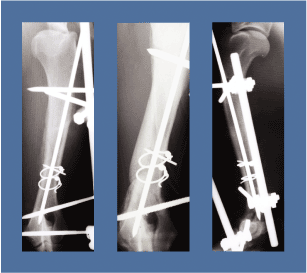

Veterinarians often combine IM pins with ESFs, which consist of a number of pins that penetrate the bone and exit through the skin to attach to rigid bars on the outside of the body. This device stabilizes the bone as it is healing, while still allowing the animal to maintain use of its limb. Several different brands of ESFs are used, such as Kirschner-Ehmer (KE) and the IMEX SK™ (SK). The variation in the brands of ESF devices involves different types of clamps that affix the pins to the bar, different types of pins that engage the bone, and different materials that comprise the components. Veterinarians must select the number, type, and configuration of ESF pins to provide adequate stabilization.

In reviewing the analysis results, von Mises stresses at the bone/pin interface and deflections at the gap between the pin and bone were especially important. The first study that compares KE and SK unilateral ESFs with IM pins has been completed. The results were validated with mathematical methods, including convergence and patch testing, and against data from laboratory testing. Comparing other variations in the IM pin/ESF configuration is an ongoing project that will provide veterinarians with improved solutions for treating animal fractures in the future.